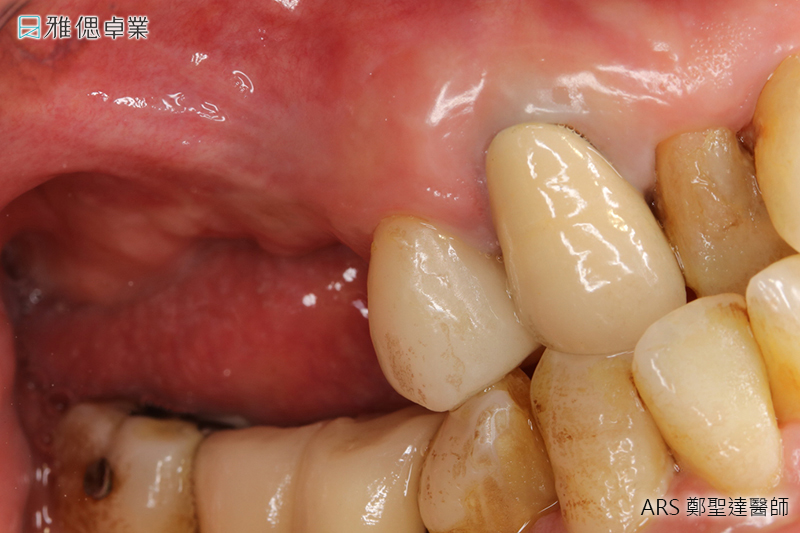

STEP3 牙齦塑形

植體在人體內3個月後,骨整合已經足夠支持咬合力,為了塑造未來牙套的牙齦型態,醫師會在植體上端接入牙齦成形帽,使牙齦生長為理想形狀。

STEP4 取得牙套(假牙)主要模型

醫師會為您的植體設計客製化的支台齒(連結人工植牙與假牙),來支撐牙套,並且會為您和原本的牙齒進行比色,讓患者植牙完成時,假牙顏色不會和真牙顏色有所落差。